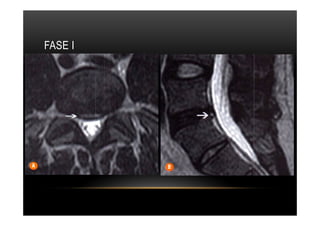

FASE I

•  Tipo I Sinal de RM: Edema

•  Tipo I

•  Alterações caracterizadas por diminuição da intensidade do sinal em Tl e aumento de

sinal em T2 traduzindo padrão de edema da medular óssea associado a inflamação

aguda ou subaguda.

•  Histopatologicamente corresponde a irregularidades e fissuras dos platôs vertebrais e

tecido fibroso vascularizado com edema da medula óssea. Após a administração de

contraste, obsenva-se realce que às vezes pode envolver o disco, possivelmente

relacionado com o tecido fibroso ,vascularizado nas adjacências da medula óssea.

•  Dor / incapacidade funcional

•  Modic I pode evoluir para Modic II ou III em 1 ano

•  Necessário diferenciar de espondilodiscite.